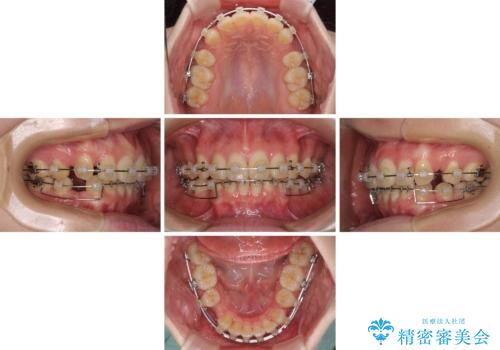

- クリアブラケット

- 3年10ヶ月

- 30回以上

- 下顎の前歯が上顎の歯肉に咬みこむくらいに突出した上顎前歯を気にして来院された患者様です。

口元の突出感はないものの、上顎前歯が前方に傾斜して突出しており、前後に大きなズレがあり非常に深い咬み合わせとなっていました。

前突間を改善するため、上顎左右の第一小臼歯を抜歯してワイヤー装置にて矯正治療を行うこととしました。

深い咬み合わせは上顎前歯を引っ込ませる大きな障害となるため、咬み合わせの改善が非常に重要となります。やや期間はかかりましたが、当初狙った通りの仕上がりで治療を終えることができました。